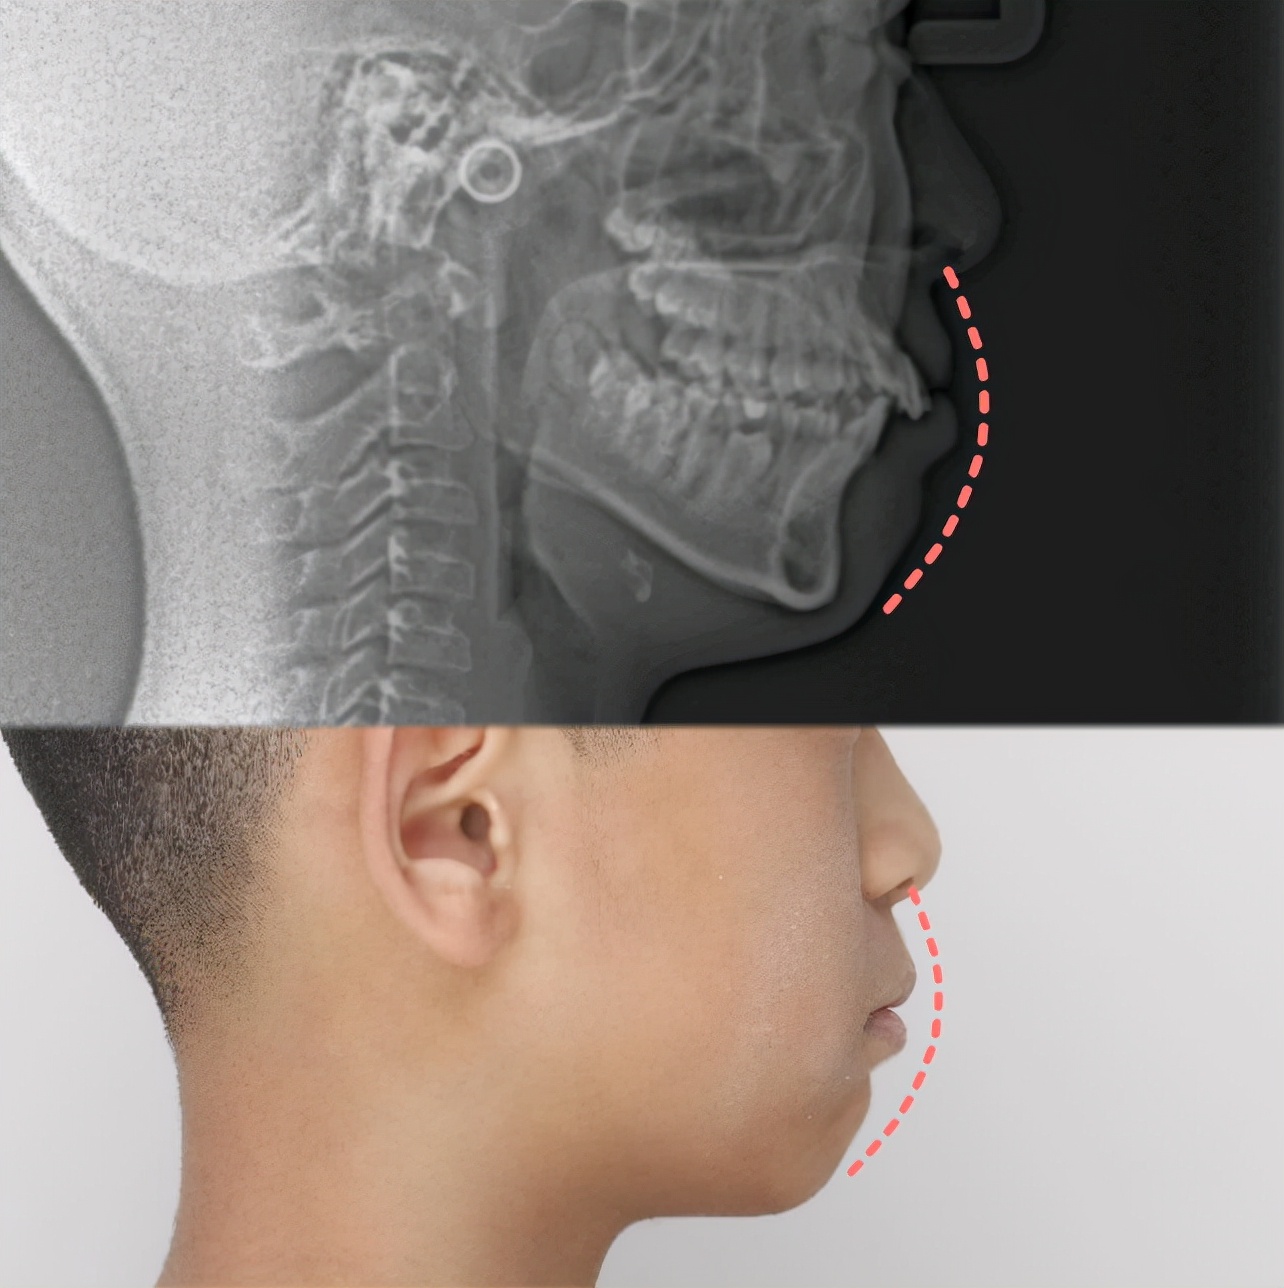

从头颅侧位片可以看到,小朋友上前牙比较唇倾,整个下颌骨处于靠后位置,闭唇时上下嘴唇比较紧张,所以显得没有下巴颏

这位患者是一位13岁的小朋友,面诊主诉是下颌后缩。

患者下颌后缩,后牙远中关系,前牙深覆盖,上颌牙弓狭窄,下颌少一颗下切牙